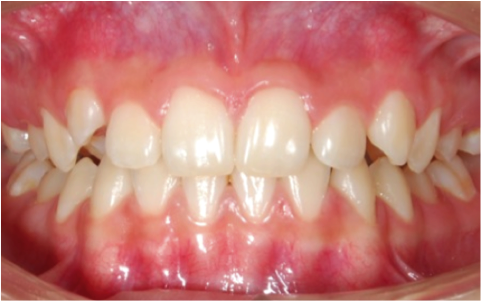

Tratamiento ortopedico para descruzar mordida

Antes